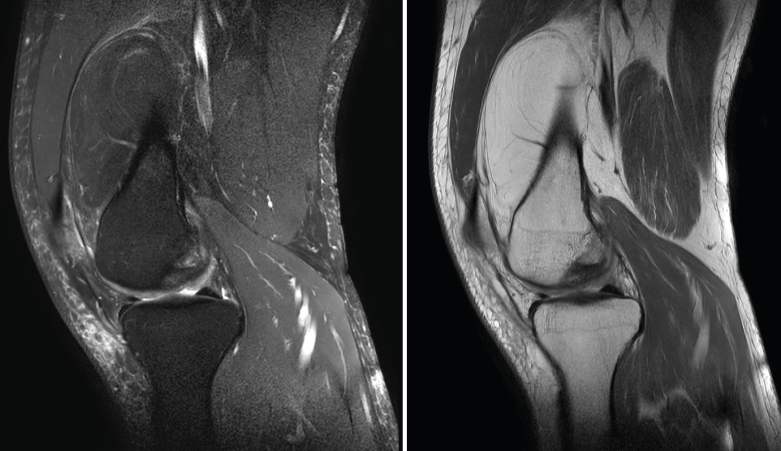

4.3. Osteocondritis

En la osteocondritis se aprecia una lesión subcondral caracterizada por resorción ósea, colapso y la formación de un secuestro.

El estudio por RM es una herramienta valiosa para diagnosticar e identificar las lesiones del cartílago. Conocer el aspecto del cartílago y saber cuánto y cuándo se lesiona, basándose en las clasificaciones actuales, permiten al radiólogo proporcionar la máxima información al clínico(20).

Figura 53. Corte de secuencia sagital (A) y axial (B) T2 Fat-Sat de RM de rodilla: lesiones osteocondrales en el fémur y la rótula.

Numerosos estudios demuestran la utilidad de la RM para definir la estabilidad o inestabilidad de la lesión en la osteocondritis, destacando su carácter no invasivo y la capacidad de valorar la progresión y la respuesta al tratamiento(21)(Figuras 53 y 54).

Figura 54. Corte de secuencia T1 y T2 Fat-Sat coronal de resonancia magnética: gran osteocondritis en el cóndilo femoral interno con edema en la medular adyacente.